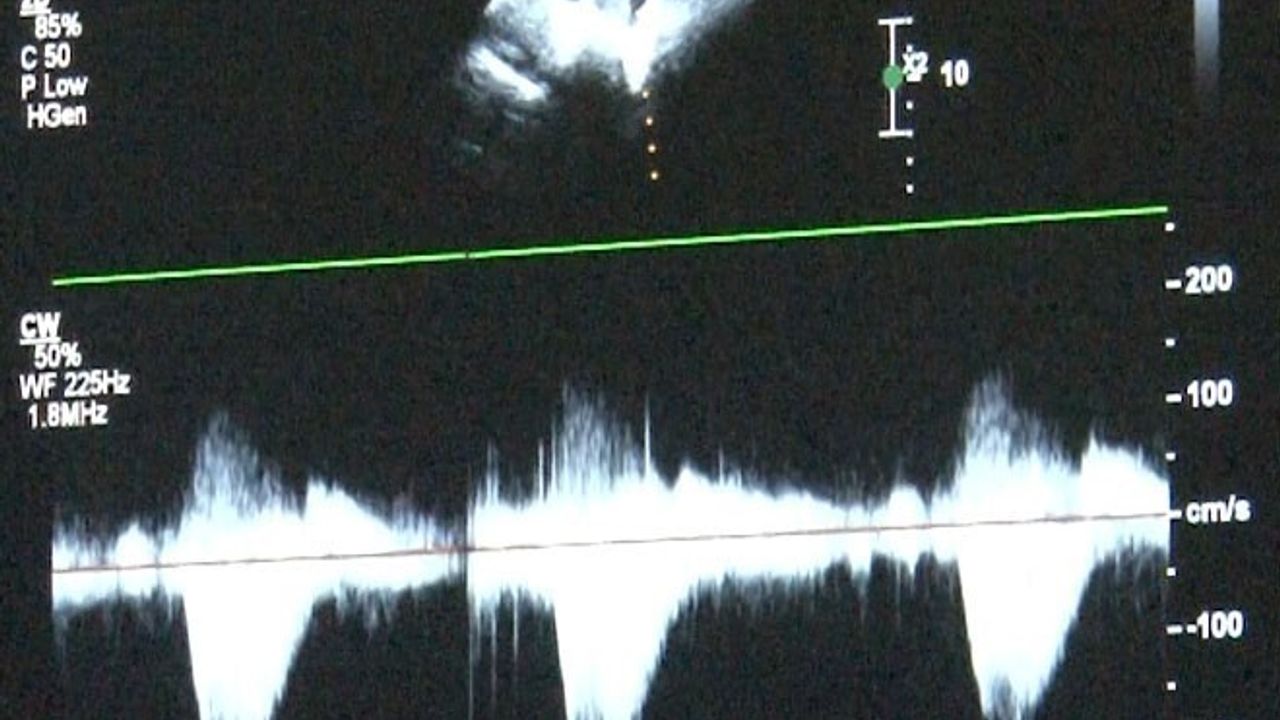

Türkiye'de doğan bebeklerin bir kısmı doğumsal kalp hastalıkları ile dünyaya gelmekte. Dr. Damla Gökçeer Akbulut, doğumsal kalp hastalığı teşhisi için zamanında tetkiklerin yapılmasının yaşamsal öneme sahip olduğunu belirtiyor. "Anne karnındaki fetal ekokardiyografi ile erken tespit mümkün," dedi.